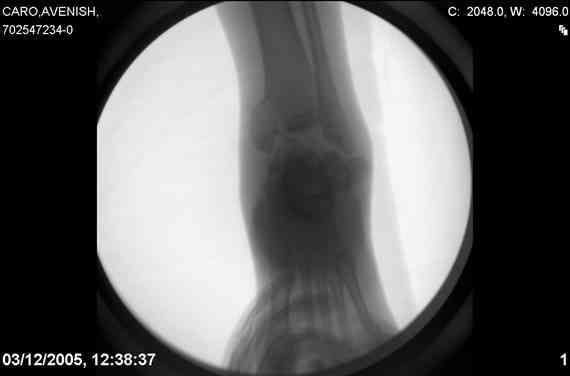

ya by popytalsya sobrat talus anatomichno,seichas pozdno operirovat iz za oteka,po etomy distrakziya apparatom budet optmalna.Posyalu vam podobyai moi sluchai.

14 years old girl

Fall from height ( 3rd floor)